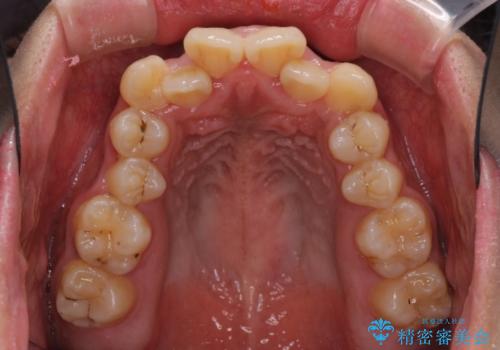

- 八重歯と上下前歯のでこぼこを気にして来院された患者様です。

上下前歯部叢生のスペース獲得のため、上下顎左右小臼歯各1歯(計4本)と全ての親知らずを抜歯して、矯正治療を行うこととしました。